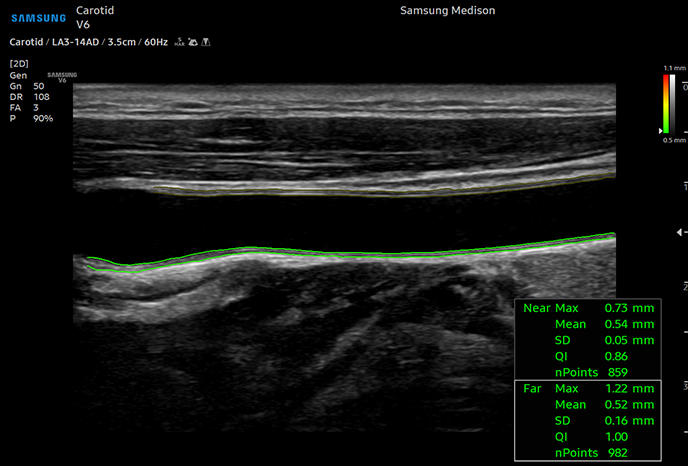

하이앤드 초음파 장비를

활용한 정밀 심장 검사

심장 질환 진단에서 가장 중요한 것은 ‘심장의 상태를 얼마나 정확하게 볼 수 있느냐’입니다. 저희 센터는 대학병원급 하이앤드 초음파 장비를 도입하여, 실시간 3D 렌더링으로 정밀 진단이 가능하며, 심장의 구조·혈류·기능을 실시간 고해상도로 관찰합니다.

미세한 판막 움직임, 혈류 속도 변화, 심방·심실 크기와 수축력까지 정밀하게 분석할 수 있어, 심장질환의 조기 발견과 치료 계획 수립에 큰 차이를 만듭니다.